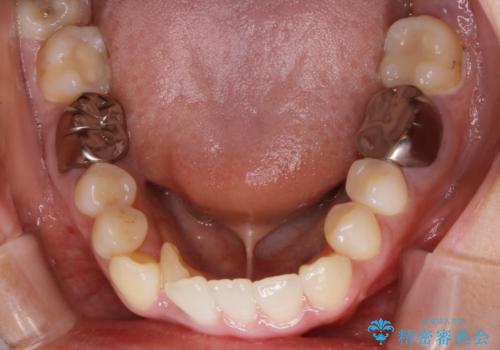

【非抜歯】インビザライン 隠れた前歯を並べる矯正治療

- 前歯のガタつき・奥に隠れてしまっている歯の矯正治療を希望されて初診来院されました。

顔貌的に口元を下げたいといった希望はなく抜歯はなるべく避けたいとのご要望からマウスピース装置(インビザライン)での治療を行うこととなりました。